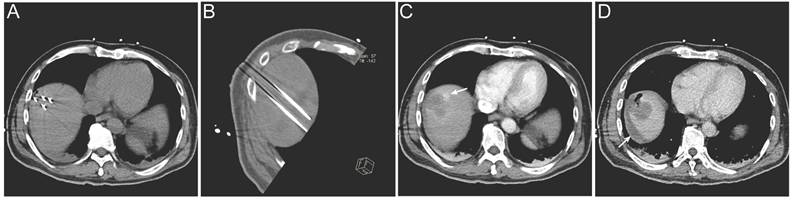

Lesions located in high-risk anatomical regions were comparably distributed between the two groups, with 7 lesions in the IRE group and 6 lesions in the RFA group; however, lesions in the IRE group were more frequently adjacent to major vessels or the hepatic hilum (Table 4). Regarding treatment safety, no deaths within 30 days after treatment were recorded and no severe complications were observed in the RFA group. In the IRE group, one patient developed ablation-related bile duct dilatation and four patients experienced hemorrhage. All adverse events were successfully managed with routine symptomatic treatment (Table 3). A representative case is shown in Figure 6. Intra-procedural images demonstrate electrode placement (Figure 6A, B). Post-ablation arterial-phase imaging demonstrates focal contrast extravasation at the ablation margin, and perilesional fluid attenuation is observed on delayed-phase imaging (Figure 6C, D).

Figure 6

Representative imaging of procedure-related complication following IRE treatment. (A, B) Intra-procedural electrode placement shown on an axial CT image (A) and an oblique multiplanar reconstructed (MPR) CT image (B); (C) Immediate post-ablation arterial-phase contrast-enhanced CT demonstrating focal contrast extravasation at the ablation margin (arrow); (D) Post-ablation delayed-phase contrast-enhanced CT demonstrating perilesional fluid attenuation (arrow).

Int J Med Sci Image